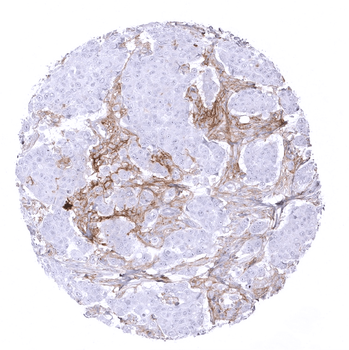

In the placenta, PD-L1 staining is predominantly seen at the surface membrane of the syncytiotrophoblast.